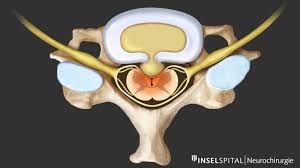

Bandscheiben op lws 4 5. Sie kommen meist zwischen den Wirbeln LWK Lendenwirbelkörper 45 und LWK 5SWK 1 Sakralwirbelkörper vor an der vorletzten und letzten Bandscheibe. Bandscheibenvorfälle sind Teil einer natürlichen Abnützung des Gewebes. Drückt der Gallertkern auf einen Rückenmarksnerven leiden Betroffene unter starken Rückenschmerzen die teilweise bis in Arme und Beine ausstrahlen.

Auch durch Vernarbungen nach der OP kann es zu Schmerzen oder Einschränkungen der Bewegung kommen. Merkblatt zur Nachbehandlung Operation an der Lendenwirbelsäule 1 4 Merkblatt zur Nachbehandlung Operation an der Lendenwirbelsäule Sehr geehrter Patientin Was Sie wissen sollten Sie leiden an einer degenerativen Erkrankung einer oder mehrerer lumbaler Bandscheiben Bandscheibenvorfall Spinalkanalstenose Wirbelgleiten. Nach einem Bandscheibenvorfall gilt es gezielt die Muskulatur im betroffenen Bereich zu stärken.

Ursachen Diagnose und Therapie. Wie der Bandscheiben-Vorfall Prolaps ist die Bandscheiben-Vorwölbung Protrusion besonders häufig in der Etage bei L4L5 zwischen dem 4.

Wenn die Physiotherapie und Medikamente nicht mehr helfen und die Schmerzen zu stark sind oder wenn der Druck auf die Nerven Ausfälle verursacht Taubheit Muskelschwäche Lähmung sollte eine Operation in Betracht gezogen werden. Bandscheibenvorfall LWS Übungen - Hier findest du 5 effektive Übungen bei einem Bandscheibenvorfall in der Lendenwirbelsäule inkl. Es geht mir zur Zeit nicht gut mache mir auch große Sorgen wie es wird in den nächsten Tagen und Wochen mit den Schmerzen und Beschwerden. Ich wurde am 4. Frank aus München in. Probieren Sie es selbst aus. Sie kommen meist zwischen den Wirbeln LWK Lendenwirbelkörper 45 und LWK 5SWK 1 Sakralwirbelkörper vor an der vorletzten und letzten Bandscheibe. Die Bandscheiben der Wirbelsäule übt eine Art Stossdämpferfunktion aus und dient der Elastizität und der Beweglichkeit der Wirbelsäule. Lendenwirbel und dem 5.